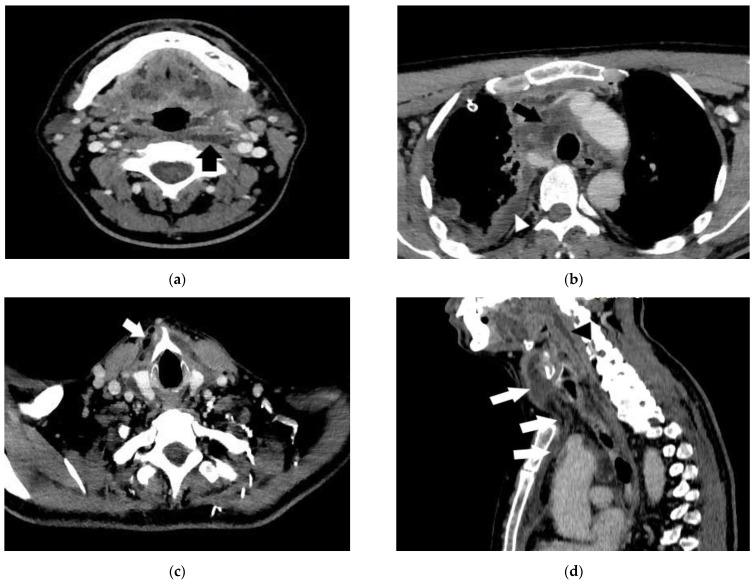

深部颈间隙化脓的治疗原则及临床演变特点——临床研究

As medical-surgical emergencies, regardless of the causal agent, deep cervical space suppurations are not only a diagnostic challenge, but also a therapeutic one. In some cases, in spite of proper therapeutic measures, extremely severe complications can develop. A 5-year retrospective study (2016-2020) was conducted on a group of 107 patients suffering from cervical suppurations, being hospitalized and treated in the ENT Clinic of the "Sf. Apostol Andrei" Emergency County Hospital of Galați. This research is a clinical-statistical study based on the experience of this ENT clinic and was carried out based on the analysis of the patients' medical records. Descriptive analysis' statistical methods of the data series collected from the clinical observation sheets were used, with the patients' informed consent for the processing of the aforementioned data, with the agreement of the Ethics Commission of the Emergency Clinical Hospital "Sf. Apostol Andrei" Galați and the College of Physicians Galați, România. The patients' clinical and multidisciplinary treatment features included in the study group are presented. The results highlight the clinical particularities of deep cervical space suppurations treatment, including under COVID-19 impact, or with other comorbidities, having consequences on the case mix index increase or directly on the costs, admittance duration and the clinical status of the patient at discharge. The conclusions of the clinical study are based on the fulfillment of the research objectives in terms of treatment and symptomatology of deep cervical space suppurations and under the impact of comorbidities (global health crisis and pandemic, triggering of comorbidities due to health care access difficulty in the context of anti-COVID-19 government-implemented measures and the infection-rate that overburdened the medical system in the early period of the pandemic). Individualized treatment of deep cervical space suppurations is recommended to be approached multidisciplinary. Of particular importance is early diagnosis combined with prompt and correctly instituted multidisciplinary treatment. In this context, an appropriate medical measure that we recommend is patient health education, as it was observed in the clinical study: most times, patients address medical services with advanced disease, hence the generally unfavorable prognosis and outcome (about 25% of patients develop unfavorable prognosis and 4% die).

作为外科急症,无论病因如何,颈部深部间隙化脓不仅是诊断上的挑战,也是治疗上的挑战。在某些情况下,尽管采取了适当的治疗措施,仍可能出现极其严重的并发症。对加拉茨“圣使徒安德烈”县急救医院耳鼻喉科收治并治疗的107例颈部化脓患者进行了一项为期5年(2016 - 2020年)的回顾性研究。本研究是一项基于该耳鼻喉科临床经验的临床统计研究,基于对患者病历的分析开展。使用从临床观察表收集的数据系列的描述性分析统计方法,在获得患者对上述数据处理的知情同意后,经加拉茨“圣使徒安德烈”急救临床医院伦理委员会和罗马尼亚加拉茨医师协会同意进行。介绍了研究组患者的临床和多学科治疗特点。结果突出了颈部深部间隙化脓治疗的临床特殊性,包括在新冠疫情影响下,或伴有其他合并症时,对病例组合指数增加或直接对成本、住院时间和患者出院时的临床状况产生的影响。临床研究的结论基于在颈部深部间隙化脓的治疗和症状学方面以及合并症影响下(全球健康危机和大流行、在政府实施的抗击新冠措施背景下因医疗服务获取困难引发合并症以及疫情初期感染率使医疗系统不堪重负)实现研究目标。建议对颈部深部间隙化脓进行多学科的个体化治疗。特别重要的是早期诊断并及时正确地开展多学科治疗。在此背景下,我们推荐的一项适当医疗措施是患者健康教育,正如在临床研究中所观察到的:大多数情况下,患者在疾病进展到晚期才就医,因此总体预后和结局不佳(约25%的患者预后不良,4%的患者死亡)。